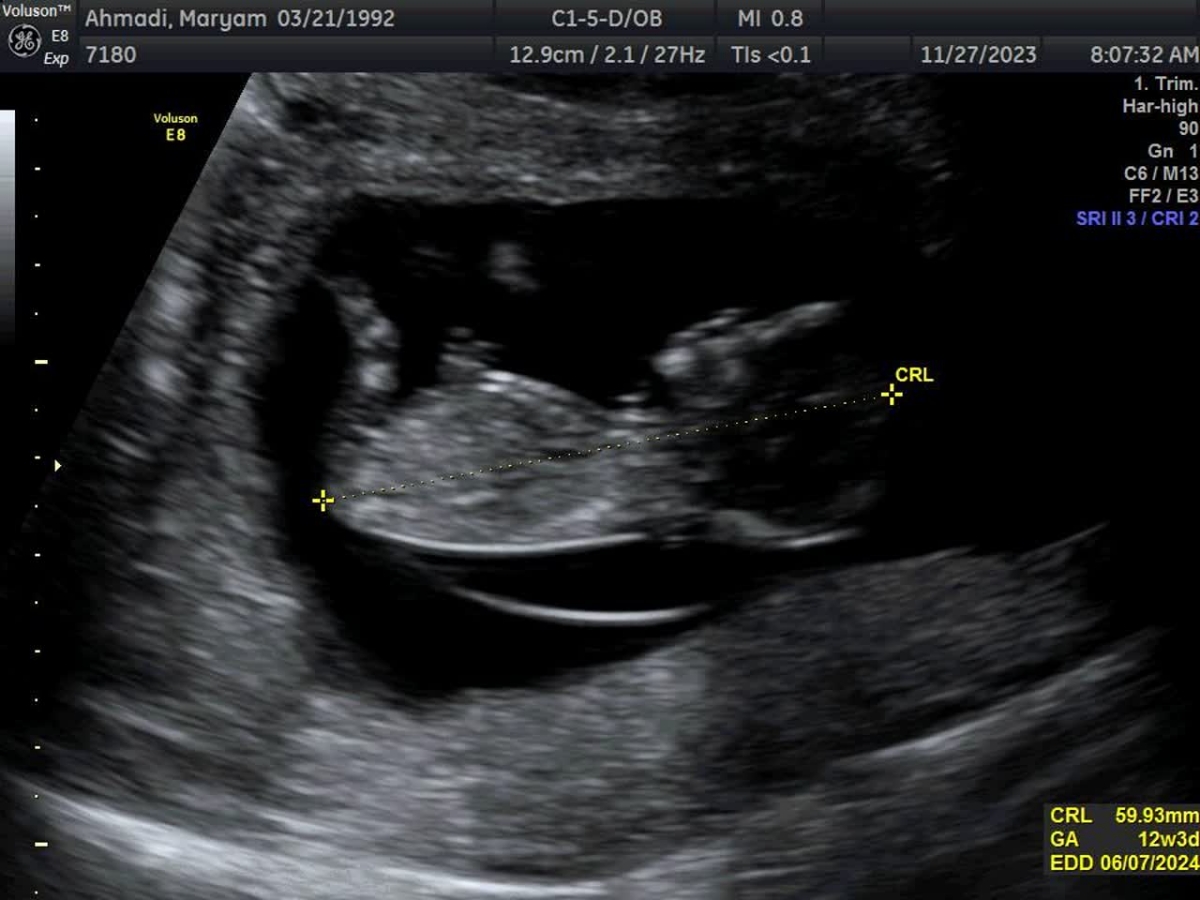

پرسش (1402/09/06):

متخصصین تعیین جنسیت لطفا بیاید 😎

ب نام خدا دختر🫠🫠

ب نظر من شبیه دختراس

پسر

اینم انگار دختره

دختر

این سونو ۱۳ هفته و۴ روز باید یه احتمال زیاد میداد دکتر

ن شبیه نیس این ب نطر من پسره

شبیه دختره